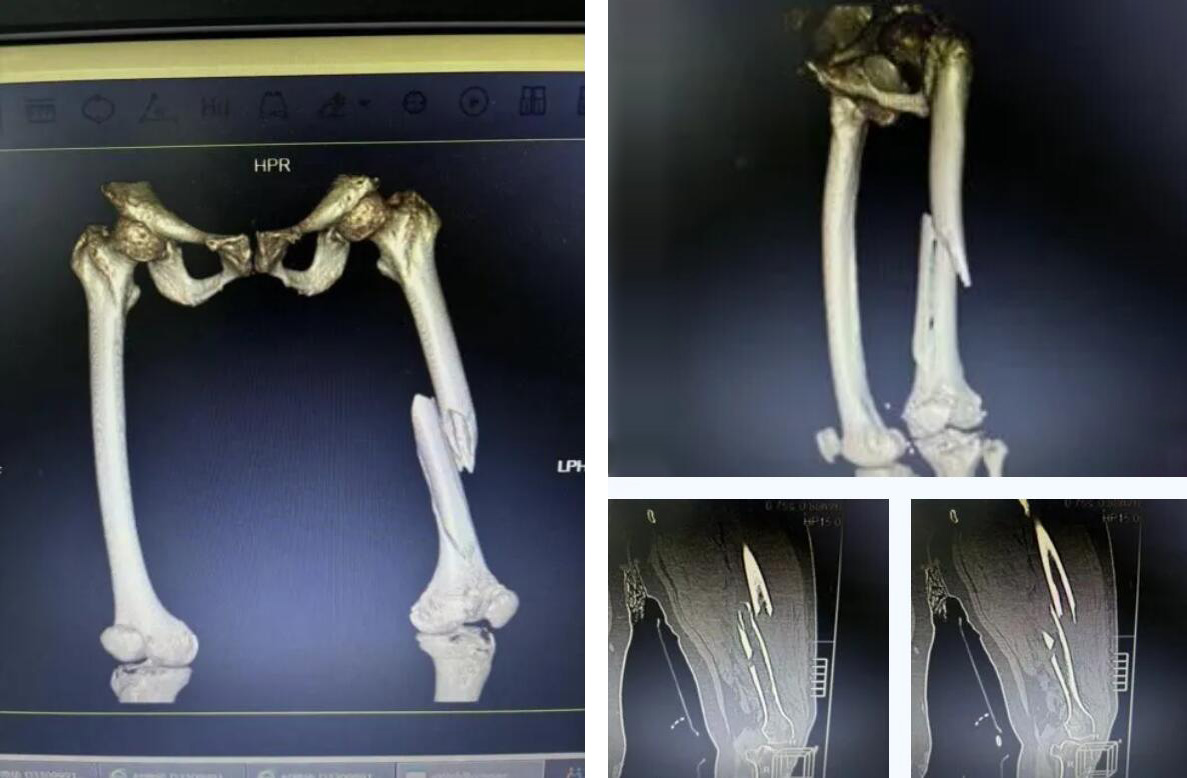

術(shù)前患者骨折CT影像

股骨,即人體的大腿骨,是全身最長(zhǎng)的骨骼,對(duì)于高齡老人,尤其是超過90歲的超高齡老人而言,髖部骨折常被稱為“人生最后一次骨折”,死亡率極高。

而俞奶奶的股骨中段的多段骨折,手術(shù)難度和風(fēng)險(xiǎn)更是呈幾何級(jí)數(shù)增加,傳統(tǒng)的開放手術(shù)創(chuàng)傷大、出血多,老人脆弱的心肺功能難以承受。